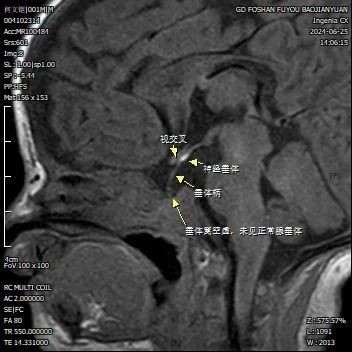

• 新生儿喂养困难,竟然是因为“它”

2025-07-22